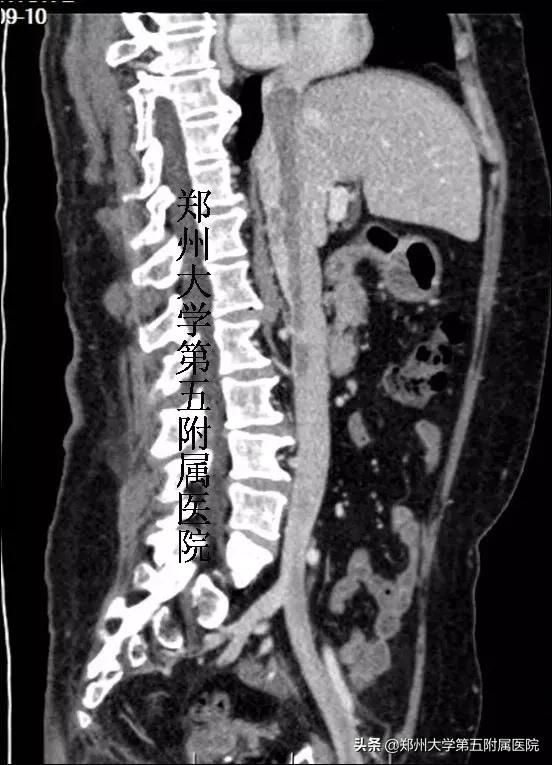

入院后,王兵教授、崔文军主任详细查看了赵女士所有的检查结果,得出一个诊断——“下腔静脉平滑肌瘤病”。下腔静脉CTV检查结果发现异常凶险,瘤体从左侧髂内静脉一直蔓延到右心房,中间段非常细,一旦继续生长或脱落断裂,很有可能瓣膜绞索、心脏梗阻、肺栓塞危及生命。仔细查看片子,左侧生殖静脉至左肾静脉也有一块血栓,如果不处理将大大增加患者复发的风险。

▲ 下腔静脉CTV提示瘤栓蔓延至心脏